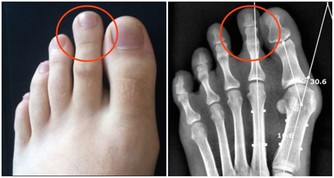

2.對骨骼的影響:偏酸的體液刺激副甲狀腺,使副甲狀腺素分泌增多,骨骼釋放到血液中的鈣增多,鈣雖然可以中和血液中的酸,但這樣長期「借」鈣的結果,會導致骨質疏鬆、骨質增生、骨骼變形及損傷等。